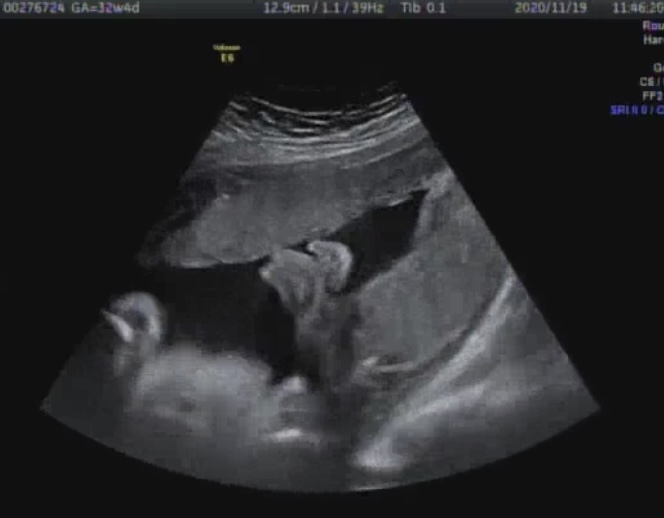

임신 34주 - 분만전검사, 막달검사비용 - 노산의 설움 - 흰머리

#임신32주 #임신34주 #임신9개월 #분만전검사 #막달검사 #막달검사비용 #노산 #노산흰머리 자가격리의 후유...